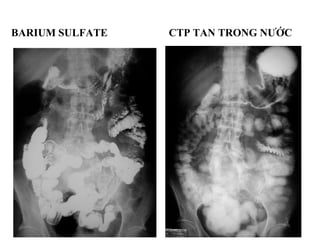

• 2 loại chính: barium sulfate và muối i-ốt (tan

trong nước)

• Sử dụng loại nào tùy chỉ định lâm sàng

BARIUM SULFATE CTP TAN TRONG NƯỚC